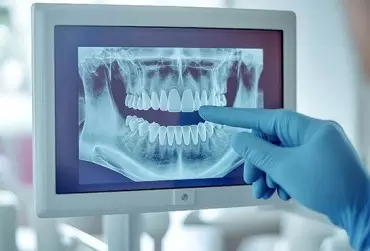

Artefakty metalowe w obrazowaniu stomatologicznym niejednokrotnie stanowią bardzo poważne wyzwanie dla dokładnej diagnostyki i planowania leczenia. Ich występowanie wynika przede wszystkim z obecności metalowych uzupełnień, implantów i aparatów ortodontycznych, co komplikuje interpretację obrazów 3D. Niestety, materiały takie jak gutaperka również powodują występowanie rozbłysków, które bez ich redukcji praktycznie uniemożliwiają trafną diagnozę. W tym artykule omówiono przyczyny powstawania artefaktów metalowych, dokonano przeglądu aktualnych metod ich redukcji oraz omówiono najnowsze technologie w tym zakresie.

Low Dose – przełom w tomografii komputerowej CBCT. Wieloletnie marzenia stały się faktem

Tomografia komputerowa CBCT niewątpliwie stała się rewolucją w diagnostyce obrazowej stosowanej przez lekarzy stomatologów. Niestety, jeszcze do niedawna wysokie dawki ekspozycji powodowały, że lekarze dentyści sięgali po mniej emisyjne formy obrazowania. Natomiast pojawiające się artefakty, w szczególności na obrazach u pacjentów z szeroko zastosowanymi metalami w jamie ustnej, skutecznie uniemożliwiały poprawną diagnozę danego przypadku.